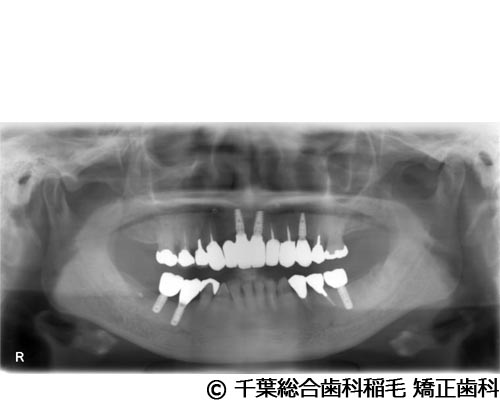

【症例2】下顎大臼歯2本インプラント埋入手術

- 治療前

- 治療後

- 治療名

- 下顎大臼歯2本インプラント埋入手術

- 費用

- 950,000円(税込)

- 期間

- 11ヵ月

治療内容

-

患者様の症状

歯茎の腫れと痛みが主訴でご来院されました。

治療法

右下第一、第二大臼歯は重度の歯周病だったため、保存が難しく、抜歯となりました。

義歯とインプラントそれぞれのメリットデメリットをお話しさせていただき、インプラントでの治療を選択されました。 -

治療結果

お痛みや腫れも和らぎ、現在も定期検診で拝見させていただいています。